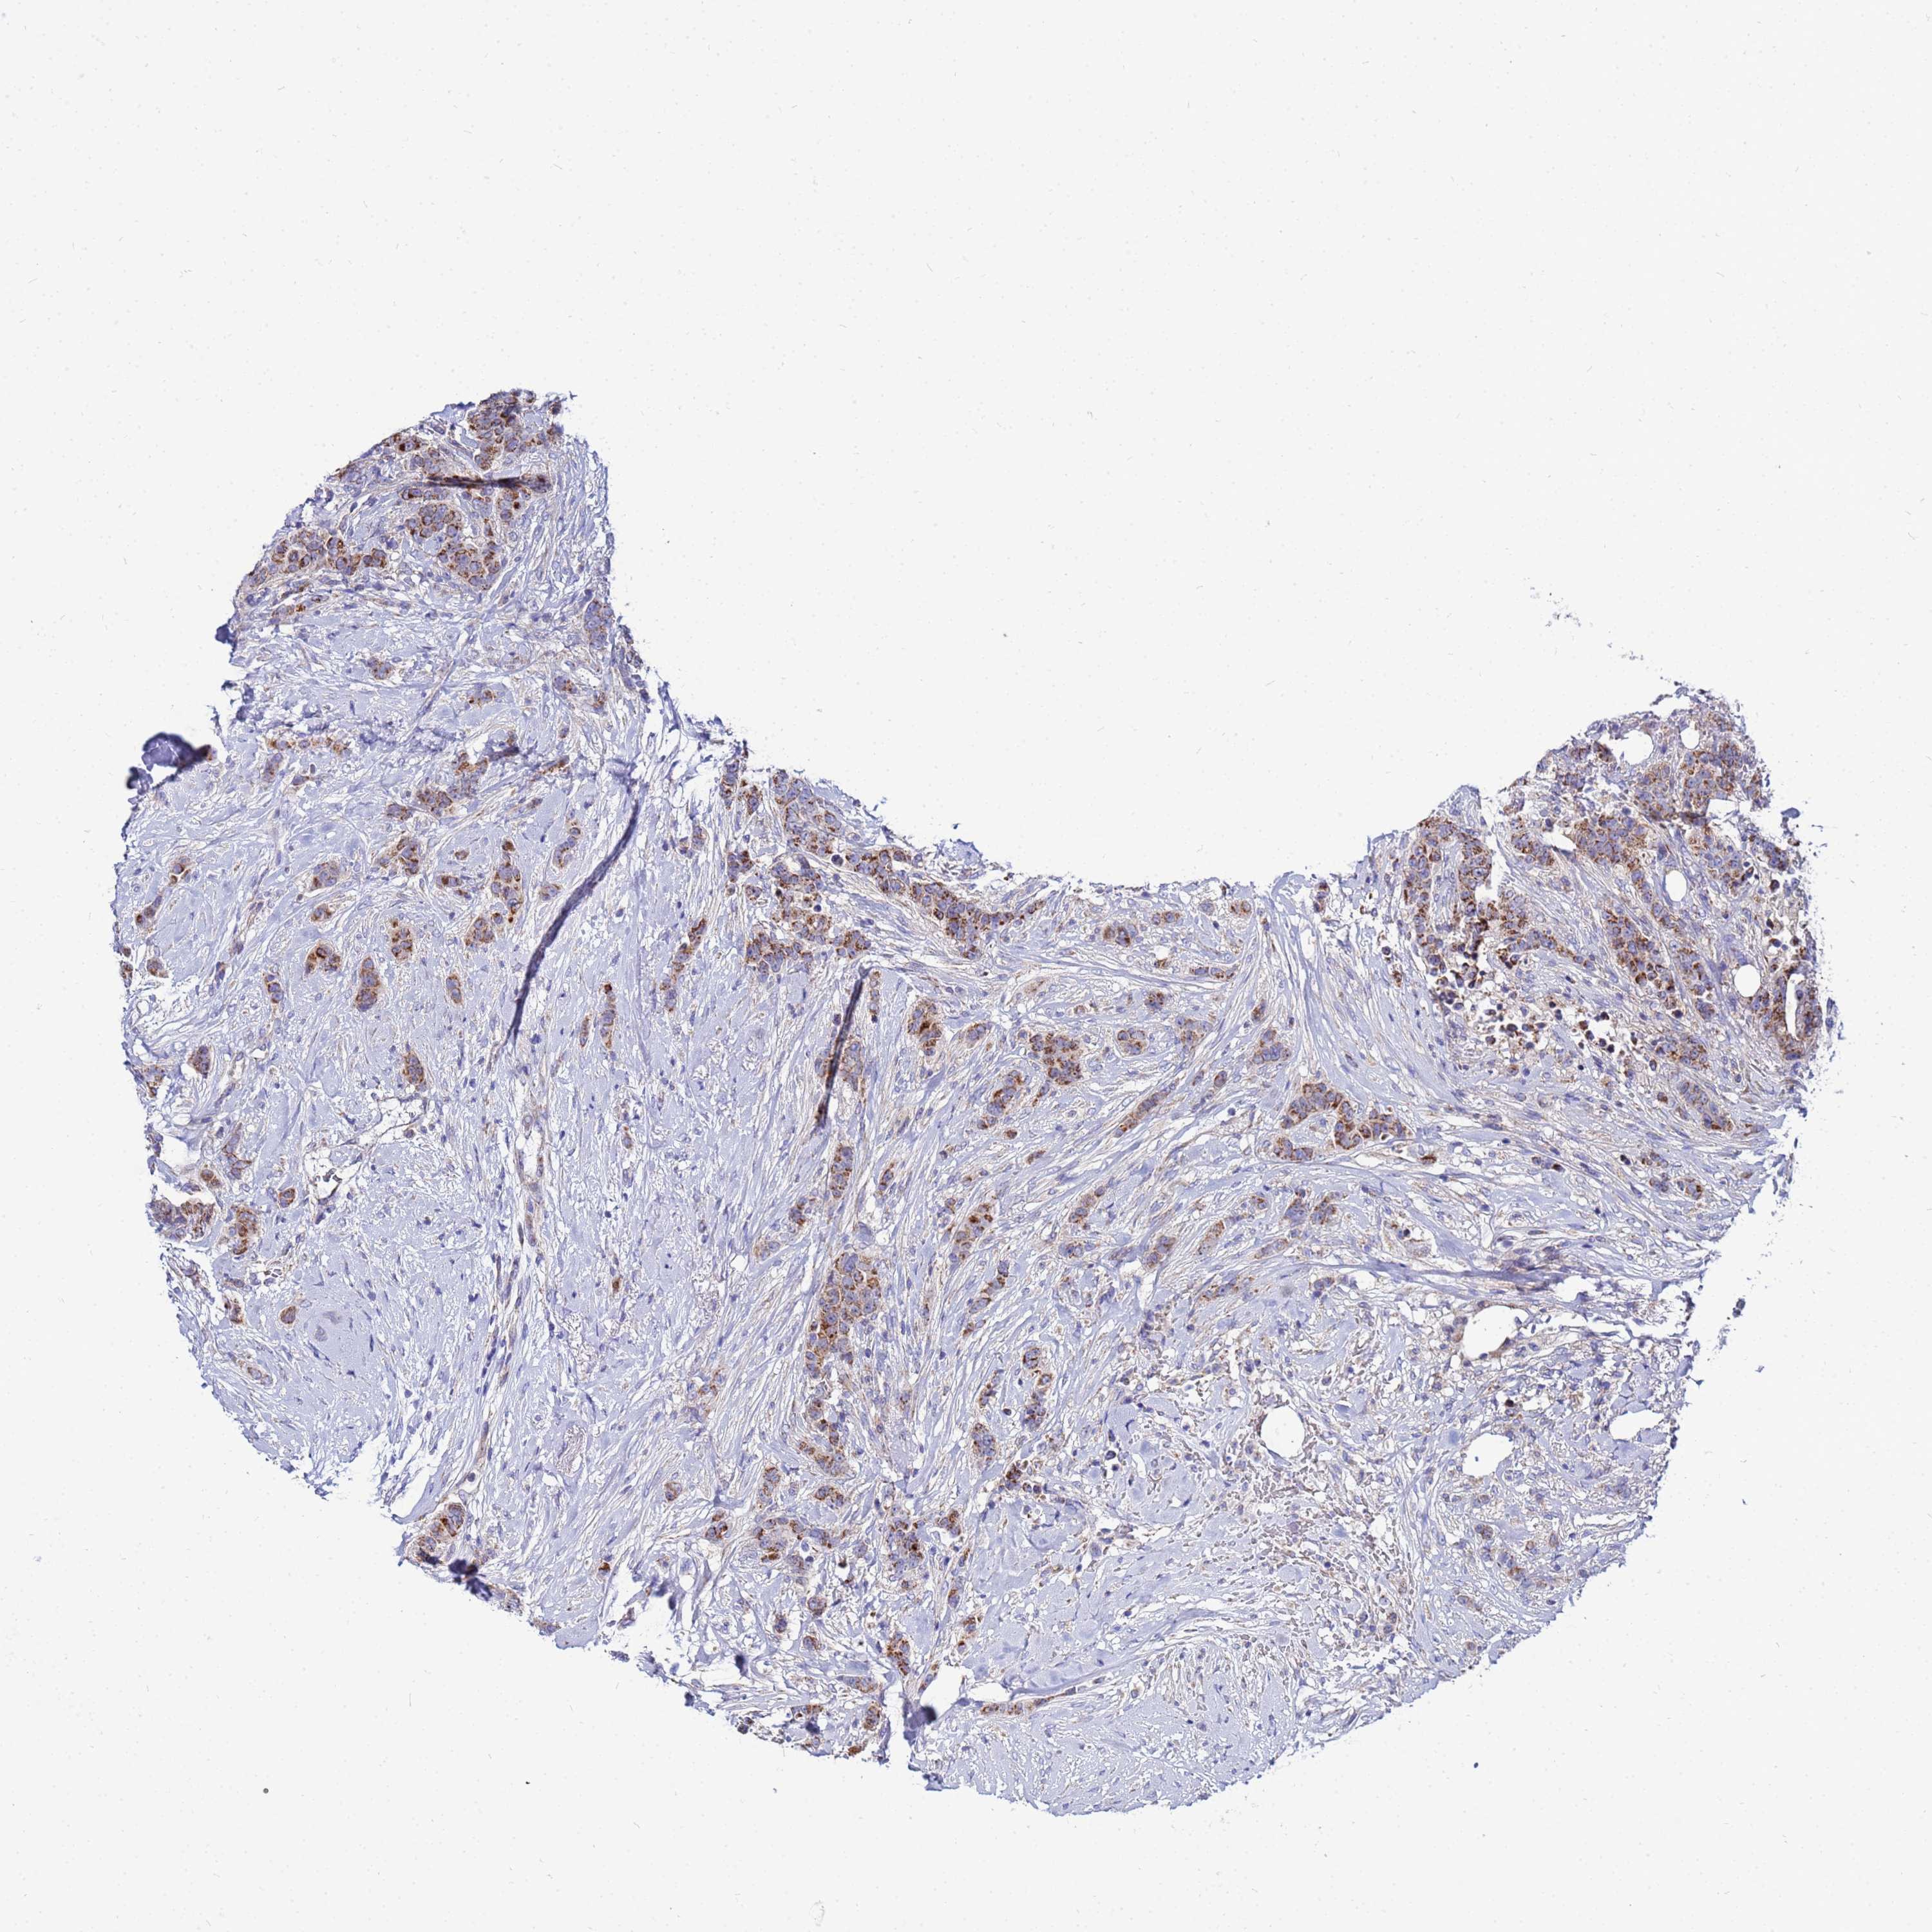

CANCER BREAST CANCER Show tissue menu

BRCA TCGA BRCA VALIDATION PROTEIN EXPRESSION